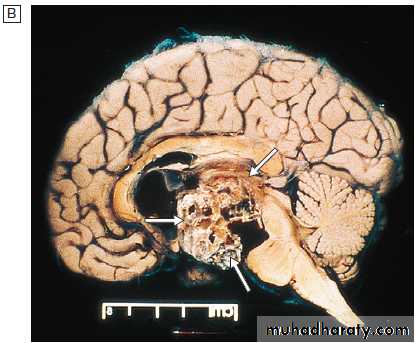

Graves’ disease.

A Bilateral ophthalmopathy in a 42-year-old man. The main symptoms were diplopia in all directions of gaze and reduced visual acuity in the left eye. The periorbital swelling is due to retrobulbar fat prolapsing into the eyelids, and increased interstitial fluid as a result of raised intraorbital pressure.B Transverse CT of the

orbits, showing the enlarged extraocular muscles. This is most obvious at the apex of the left orbit (arrow), where compression of the optic nerve caused reduced visual acuity.